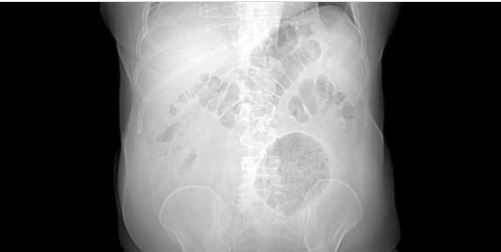

Conforme informações divulgadas pelo Hospital Municipal Salgado Filho, a formação inflamatória identificada no paciente apresentava dimensões extraordinárias, medindo 13 x 12 x 10 cm na região abdominal. Em comparação, os divertículos comuns costumam ter entre 4 e 9 cm de diâmetro.

Na publicação do estudo o médico Alexandre Fiuza, um dos autores do estudo e responsável pela cirurgia do paciente, conta que no primeiro exame clínico realizado na emergência, identificou-se a presença de uma massa flácida, palpável e dolorosa no flanco esquerdo do abdome.

Ao analisar os resultados da tomografia computadorizada, os médicos se viram surpresos com as dimensões da inflamação.

Uma semana após, a cirurgia de laparotomia exploradora (abertura de uma parte do abdômen para verificar lesões) confirmou a presença da massa inflamatória na parede abdominal e no cólon sigmoide, localizado na porção final do intestino grosso.